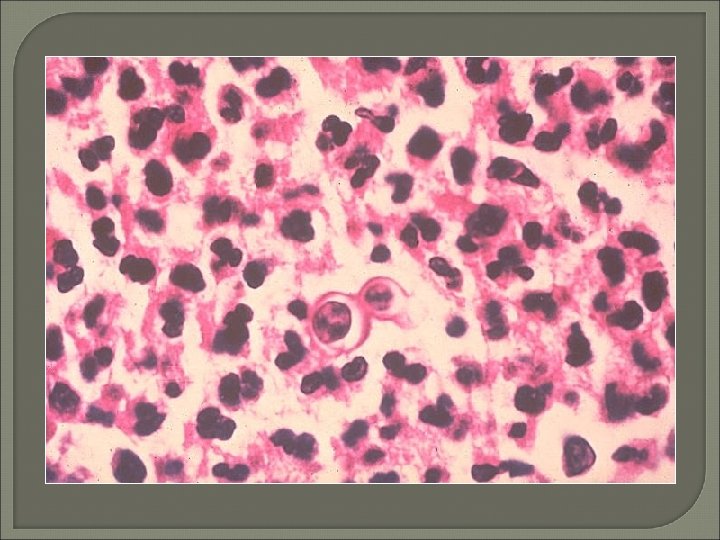

Fungal Meningitis • • India ink for cryptococcal capsular halos 50% sensitivity LA and CF antibodies now available Sensitivity as high as 96%

Primary Amoebic Meningoencephalitis (PAM) • Rare disease caused by free-living amoeba Naegleria fowleri or Acanthamoeba species • Motile Naegleria trophozoites may be seen with light microscope • Acridine orange stain can differentiate amoeba (brick red) from leukocytes (bright green)

CSF Cytology • Cytological evaluation of CSF is an effective means for diagnosing many disorders involving the central nervous system. Preparatory methods for CSF examination are discussed and normal and reactive conditions involving lymphoma, leukemia, meningeal carcinomatosis and the subarachnoid spread of primary brain tumors are evaluated by primary cytological examination of CSF